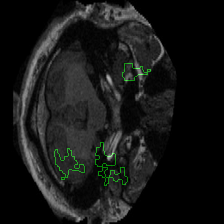

Figure 1 presents attribution maps generated using PWIG for a selection of MRI scans across all four diagnostic categories. The highlighted regions (in green) correspond to the areas that contributed most significantly to the model’s decision. Notably, we observe consistent emphasis on anatomical structures that align with clinical markers of dementia, including cortical and subcortical regions. For instance, in the moderate and mild dementia examples, the model focuses on regions exhibiting visible atrophy or abnormal morphology. In contrast, attribution maps for non-demented subjects appear more diffuse and less concentrated, reflecting the model’s detection of normal anatomical patterns.

The results in Figure 1 demonstrate that PWIG can effectively produce interpretable and clinically meaningful explanations for model predictions in medical imaging tasks.

Figure 1: PWIG attribution maps across dementia categories using the OASIS-1 dataset. Green overlays indicate regions with the highest attribution scores.